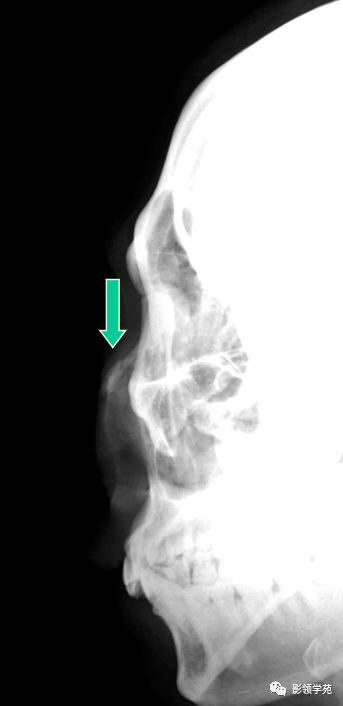

X线平片:侧位

鼻骨正常侧位